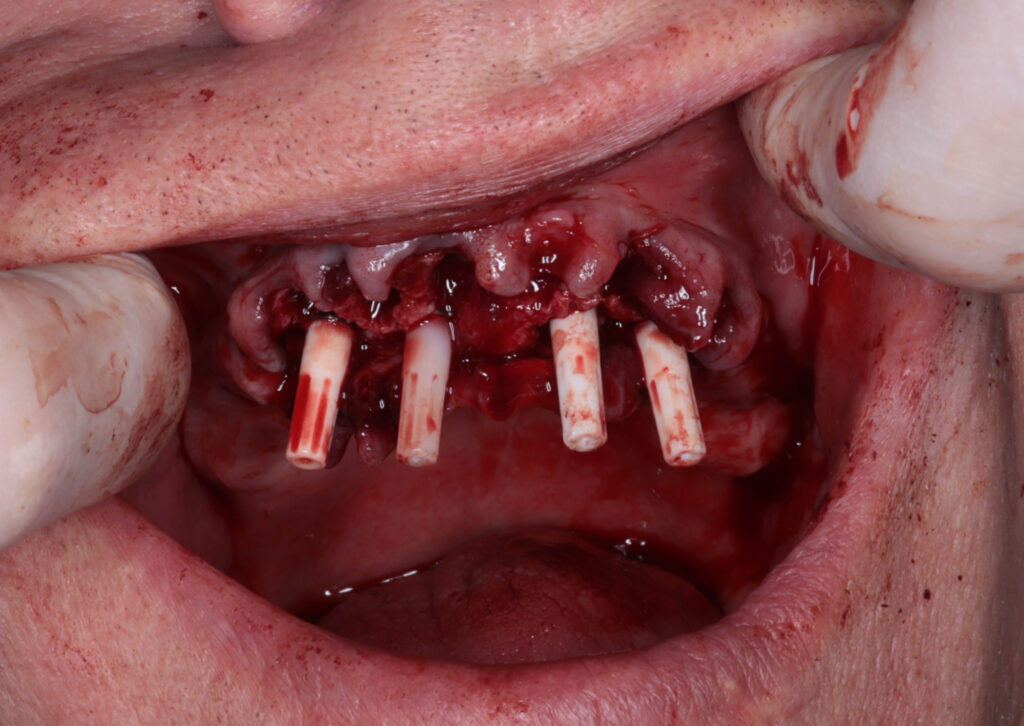

Процесс работы

Что было сделано:

На верхней челюсти была проведена комплексная имплантация по системе All-on-4,

установлены 4 имплантата Megagen AnyOne.

пациент по время имплантации

Это фото может содержать тяжелый для восприятия контент